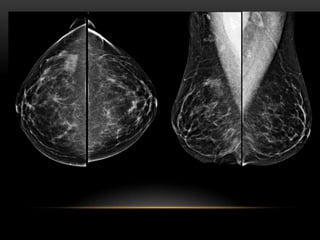

PATRÓN DE TEJIDO

PATRÓN DEL TEJIDO GLANDULAR

1. Fibroadiposo escasa cantidad(- 25 %

glándula)

3. Densidad heterogénea (51-75% glándula)

4. Extremadamente denso(+ 75% glándula)

FIBROGLANDULAR ESCASA CANTIDAD

FIBROGLANDULAR MODERADA CANTIDAD

HETEROGENEAMENTE DENSO

EXTREMADAMENTE DENSO